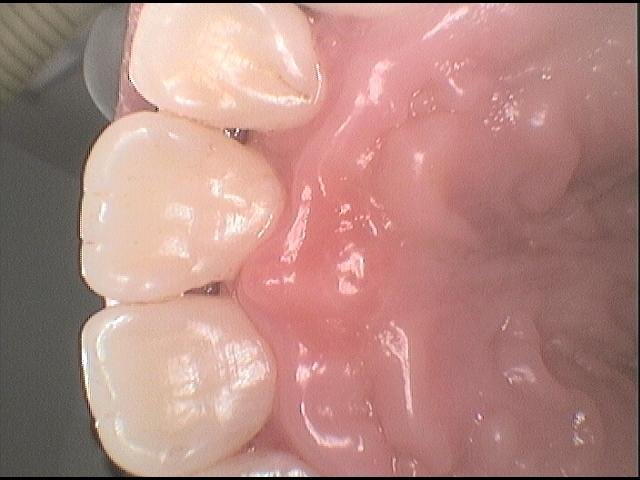

Stav po odstranění zubního kamene a zhojení zánětu dásní

Stav po profesionální dentální hygieně a správné domácí hygieně, bez známek zánětu

Čistý povrch zubů po odstranění pigmentací pomocí air-flow

Čistý povrch zubů po odstranění zubního kamene a zdravá dáseň